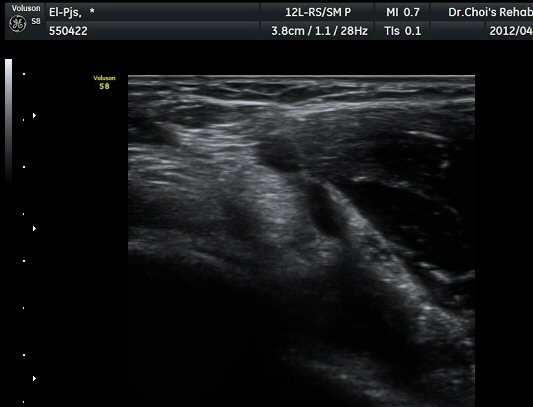

ŽÃËÀÚ¸¦ ÆÈ²ÞÄ¡ ¸»´ÜÀ¸·Î À̵¿ÇÏ´Ï À̵ιڱ٠ÈûÁÙÀÇ ºñÈÄ¿Í ÈûÁÙ ÁÖÀ§¿¡ Àú¿¡ÄÚ ¼ö¾×Àú·ù°¡ ]

°üÂûµÈ´Ù(±×¸² 2, 3, 4, 5). ŽÃËÀÚ¸¦ ¸»´ÜÀ¸·Î À̵¿ÇÒ ¶§ ŽÃËÀÚ¸¦ ¸Ó¸®ÂÊÀ¸·Î °æ»ç(tilting)½ÃÄѾß

À̵ιڱ٠ÈûÁÙ¿¡ Á÷°¢ ÀÇ ÃÊÀ½ÆÄ Á¶»ç°¡ °¡´ÉÇÏ¿© À̵ιڱ٠ÈûÁÙÀÌ °í¿¡ÄÚ·Î °üÂûµÈ´Ù.